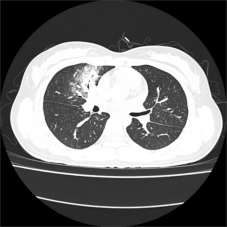

术前影像情况(左)与术后一天影像情况(右)